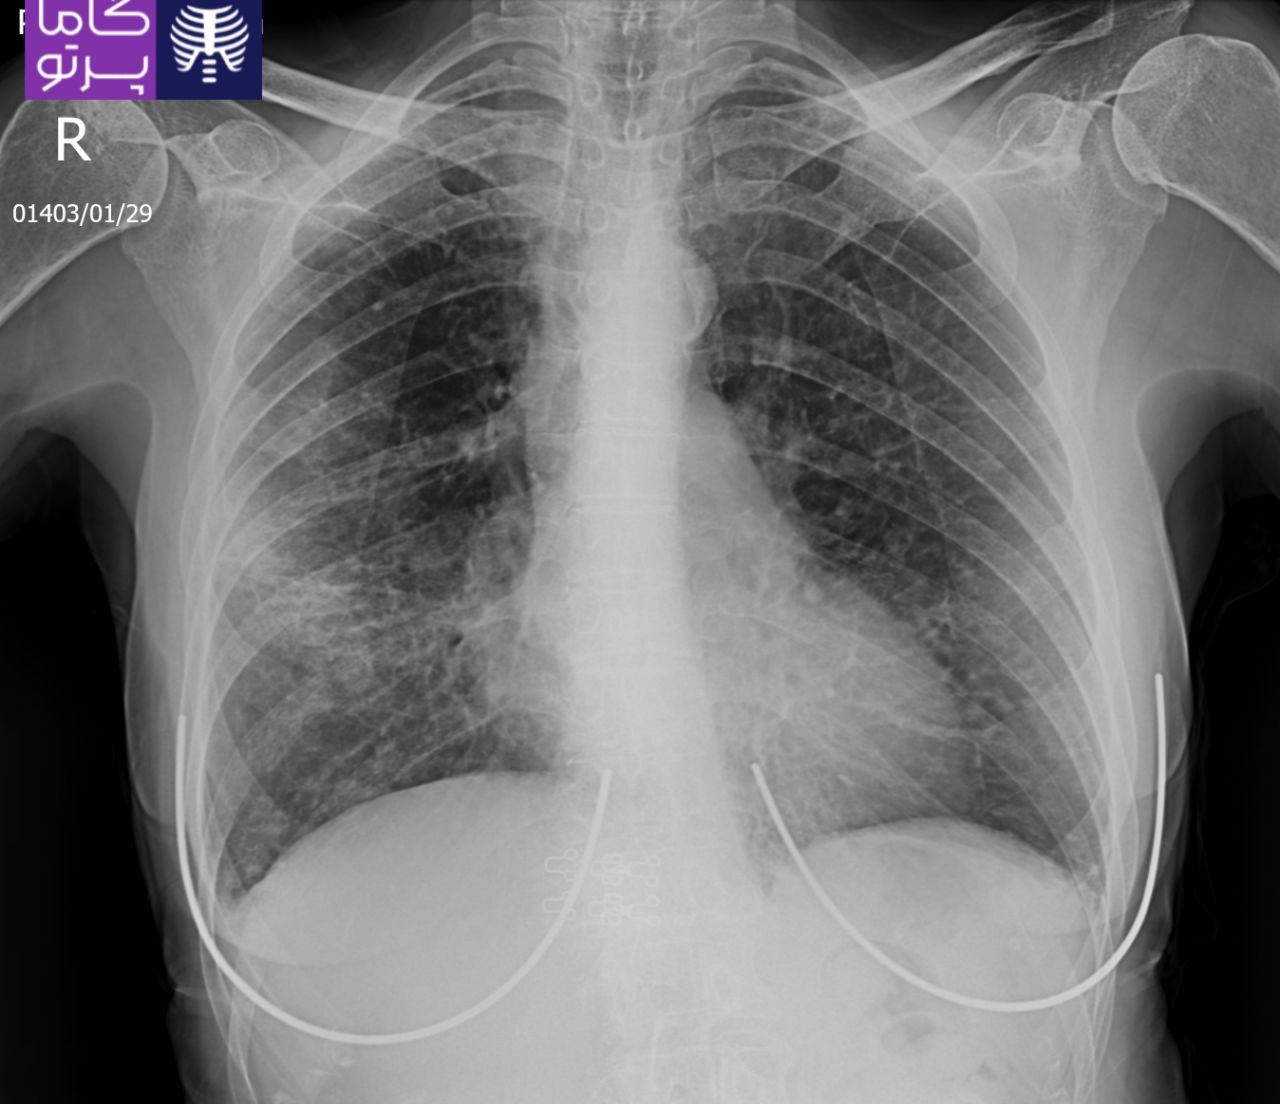

تصاویری از رادیولوژی در منزل توسط گاما پرتو

در این روش تصویر برداری یک صفحه (گیرنده یا دتکتور) در زیر عضو و قسمت مورد نظر قرار داده می شود و اشعه ایکس(دُز از اشعه جهت تشخیص) به همان قسمت که روی صفحه قرار گرفته تابنده می شود و توسط صفحه اطلاعات دریافت می شوند و همین اطلاعات پس از پردازش های لازم در نهایت عکس رادیولوژی به ما ارائه می دهد. کاربردهای رادیولوژی در منزل دقیقاً همان کاربرد رادیولوژی در بیمارستان ها می باشد از جمله بررسی انواع شکستگی ها، دررفتگی مفاصل، آرتروز مفاصل، دیدن پروتز های داخل استخوان از نظر بررسی موقعیت پروتز، آب آوردگی ریه(اِدم وافیوژن) و عفونت ریه، شکستگی دنده ها، انساد و وجود هوا در شکم و… می باشند. رادیولوژی در منزل تمام این خدمات را ارائه می دهد.